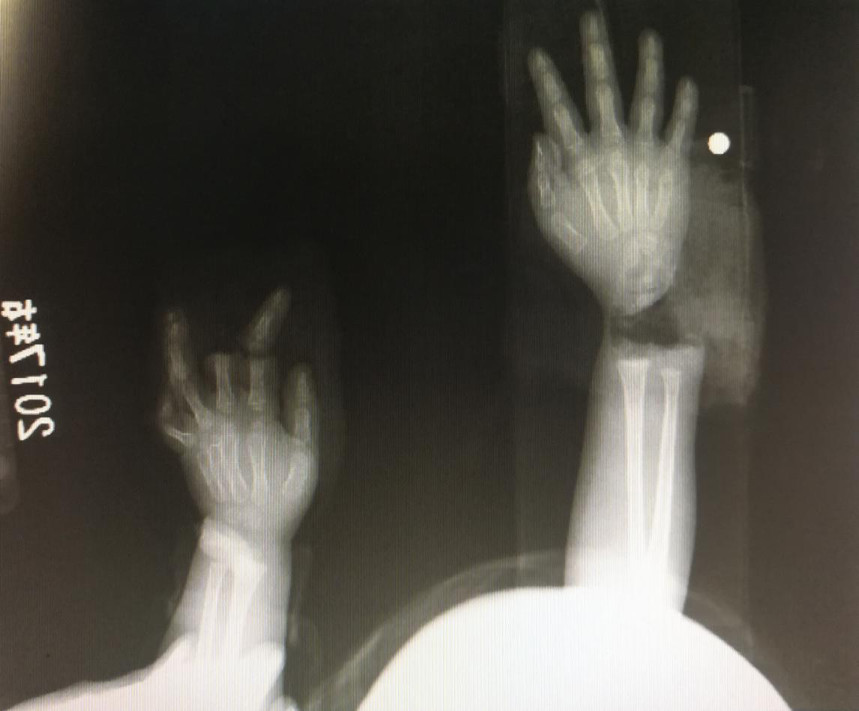

“急診在哪,急診在哪”,伴隨著一聲聲急促的問詢,一位年輕女士抱著渾身是血的小孩疾步前往急診室,懷里的小孩在疲憊與疼痛的交織下,時(shí)睡時(shí)醒。鑒于小孩的情況,急診醫(yī)生迅速安排給小孩拍了X光片,影像片結(jié)果顯示小孩左手手腕完全離斷,右手中、食指離斷,距離事發(fā)時(shí)間已經(jīng)3個(gè)多小時(shí),需盡快安排手術(shù)。